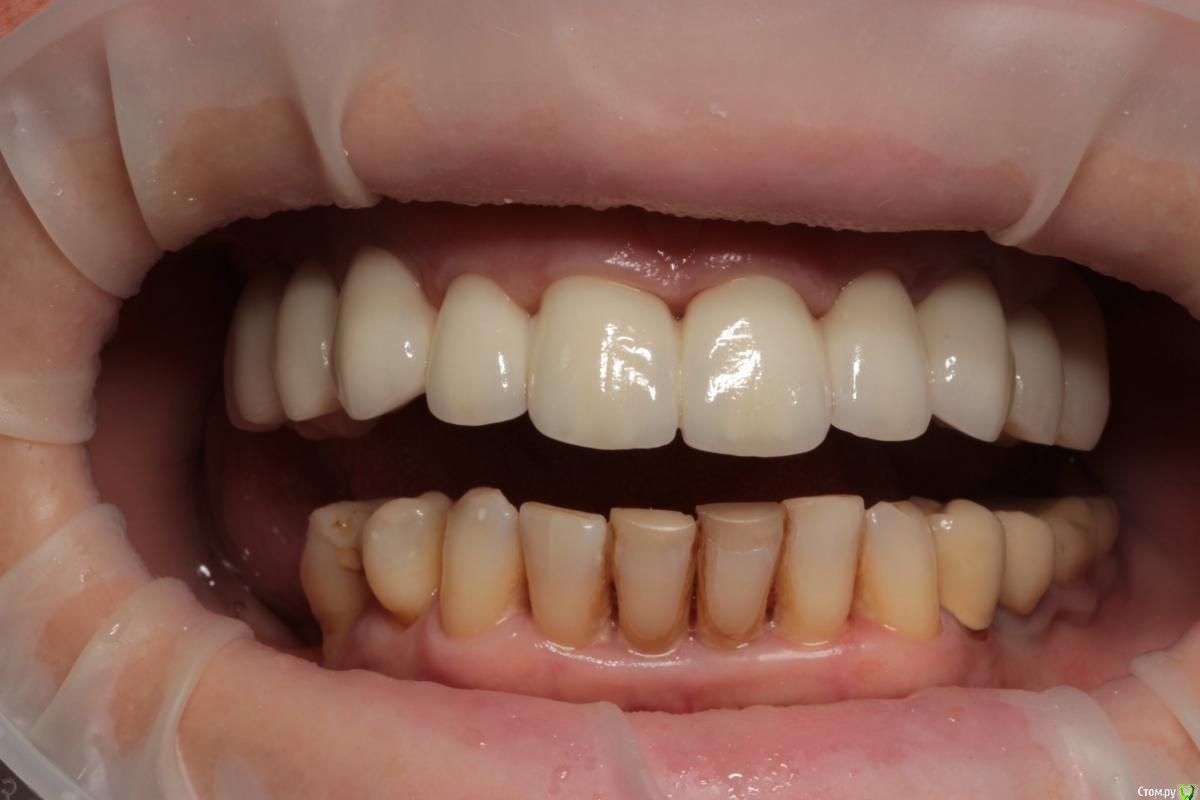

Популярный пост Abuk Опубликовано 24 ноября, 2015 Популярный пост Поделиться Опубликовано 24 ноября, 2015 Планировали 8 имплантатов.Буду рад конструктивной критике.Фото с мокап.Через 6 днейДалее хотели поставить 6 ки, она отказалась (не хотели синусы)и решили все по-другому .Через 2мес пришла с отколотыми консолями )Прошу прощения ,что ортопедию выложил не в том разделе), не хотел делить. 26 1 Ссылка на комментарий

Abuk Опубликовано 24 ноября, 2015 Автор Поделиться Опубликовано 24 ноября, 2015 (изменено) Радикально Вы. Что оставили ей после имплантации-это инд аббатменты? На них мокап одели и нагрузили сразу? У всех был торк хороший? Или это временные абб? Что за систему использовали? В планах консоль назад, правильно я понимаю?Спасибо.увидев такую работу,сам так же подумал бы). Но там подвижность 2-3 ст. ближе к 3. Мосты болтались ,2 ки в хлам. 1 ки только стабильны. Снимал мосты,проводил кюретаж. Решил дернуть.Абатманы временные, тех. сделал на них коронки. Система анкилоз. Работа,на посл. фото, постоянная . Имплы в области 4 и по одному моляру ,консоли. Мок ап был до имплантации . По нему шаблон. Стабильность 15 -20 на 23 , остальное больше 30. Изменено 24 ноября, 2015 пользователем Abuk 1 Ссылка на комментарий

Abuk Опубликовано 24 ноября, 2015 Автор Поделиться Опубликовано 24 ноября, 2015 Вы лунки тоже аугментиовали?Хирургия понравиласьДа, спасибо. Если не сложно, напишите что вам не понравилось в ортопедии.Техничка мне самому не очень , хотя многим ,включая пациента, понравилась Ссылка на комментарий